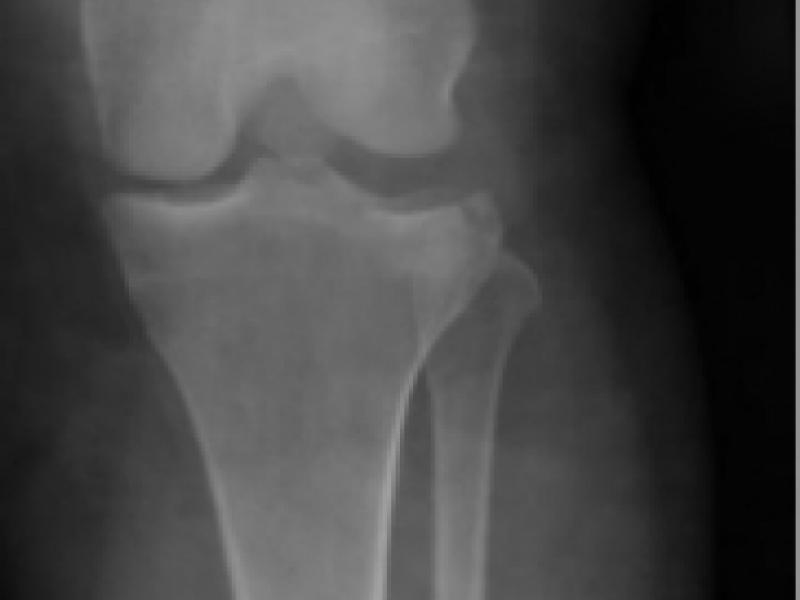

A 40 yo female presents with knee pain after climbing a